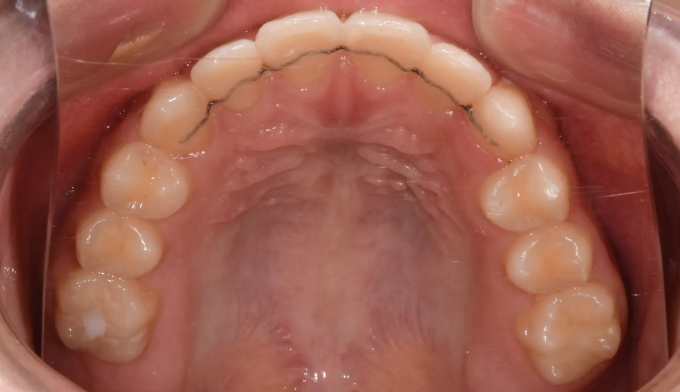

공간 확보 후 치아를 배열하여 교정 마무리 하였습니다.

이때 치아가 뻗쳐보이거나 입이 나와보이게 확장하지 않아야 합니다.

총 교정기간은 22개월 소요되었습니다.